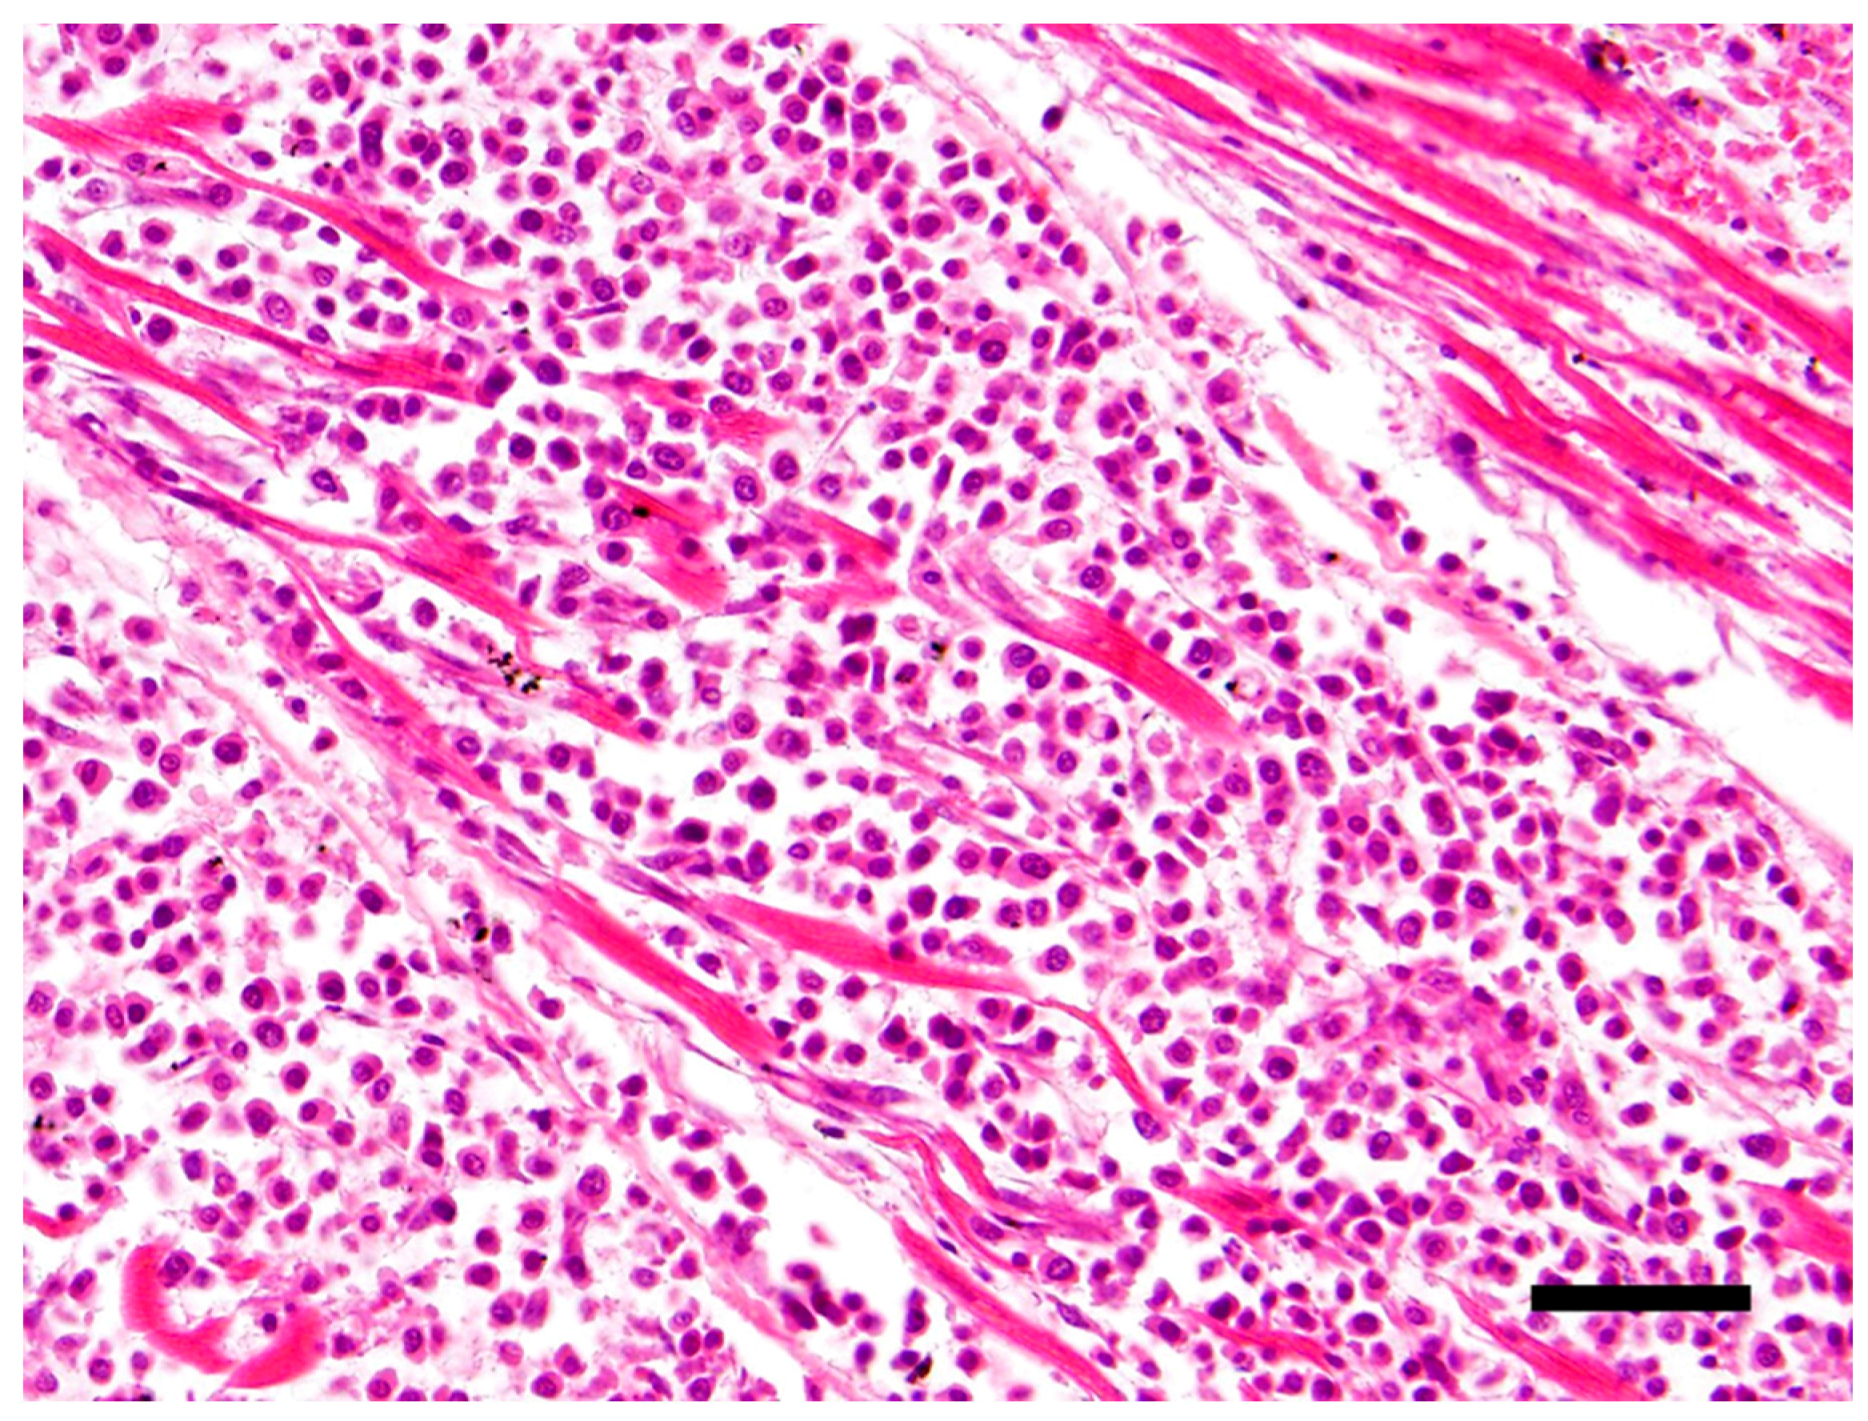

The main histological finding was present in the heart. There was effacement of the myocardial architecture by an invasive population of round cells that separated degenerating myofibers (Figure 1). These neoplastic round cells showed marked anisocytosis and anisokaryosis, and had moderate to large amounts of bright eosinophilic cytoplasm and rare perinuclear clearing. The nuclei were round with speckled heterochromatin and mitoses averaged 4 per 10 hpf (high power (400x) fields). These neoplastic cells had a distinct plasmacytoid morphology (Figure 2).

Figure 1.

Effacement of the myocardial architecture by an invasive population of round cells that separate degenerating myofibers. Hematoxylin and eosin (H&E) stain 40×, Bar = 50μm.